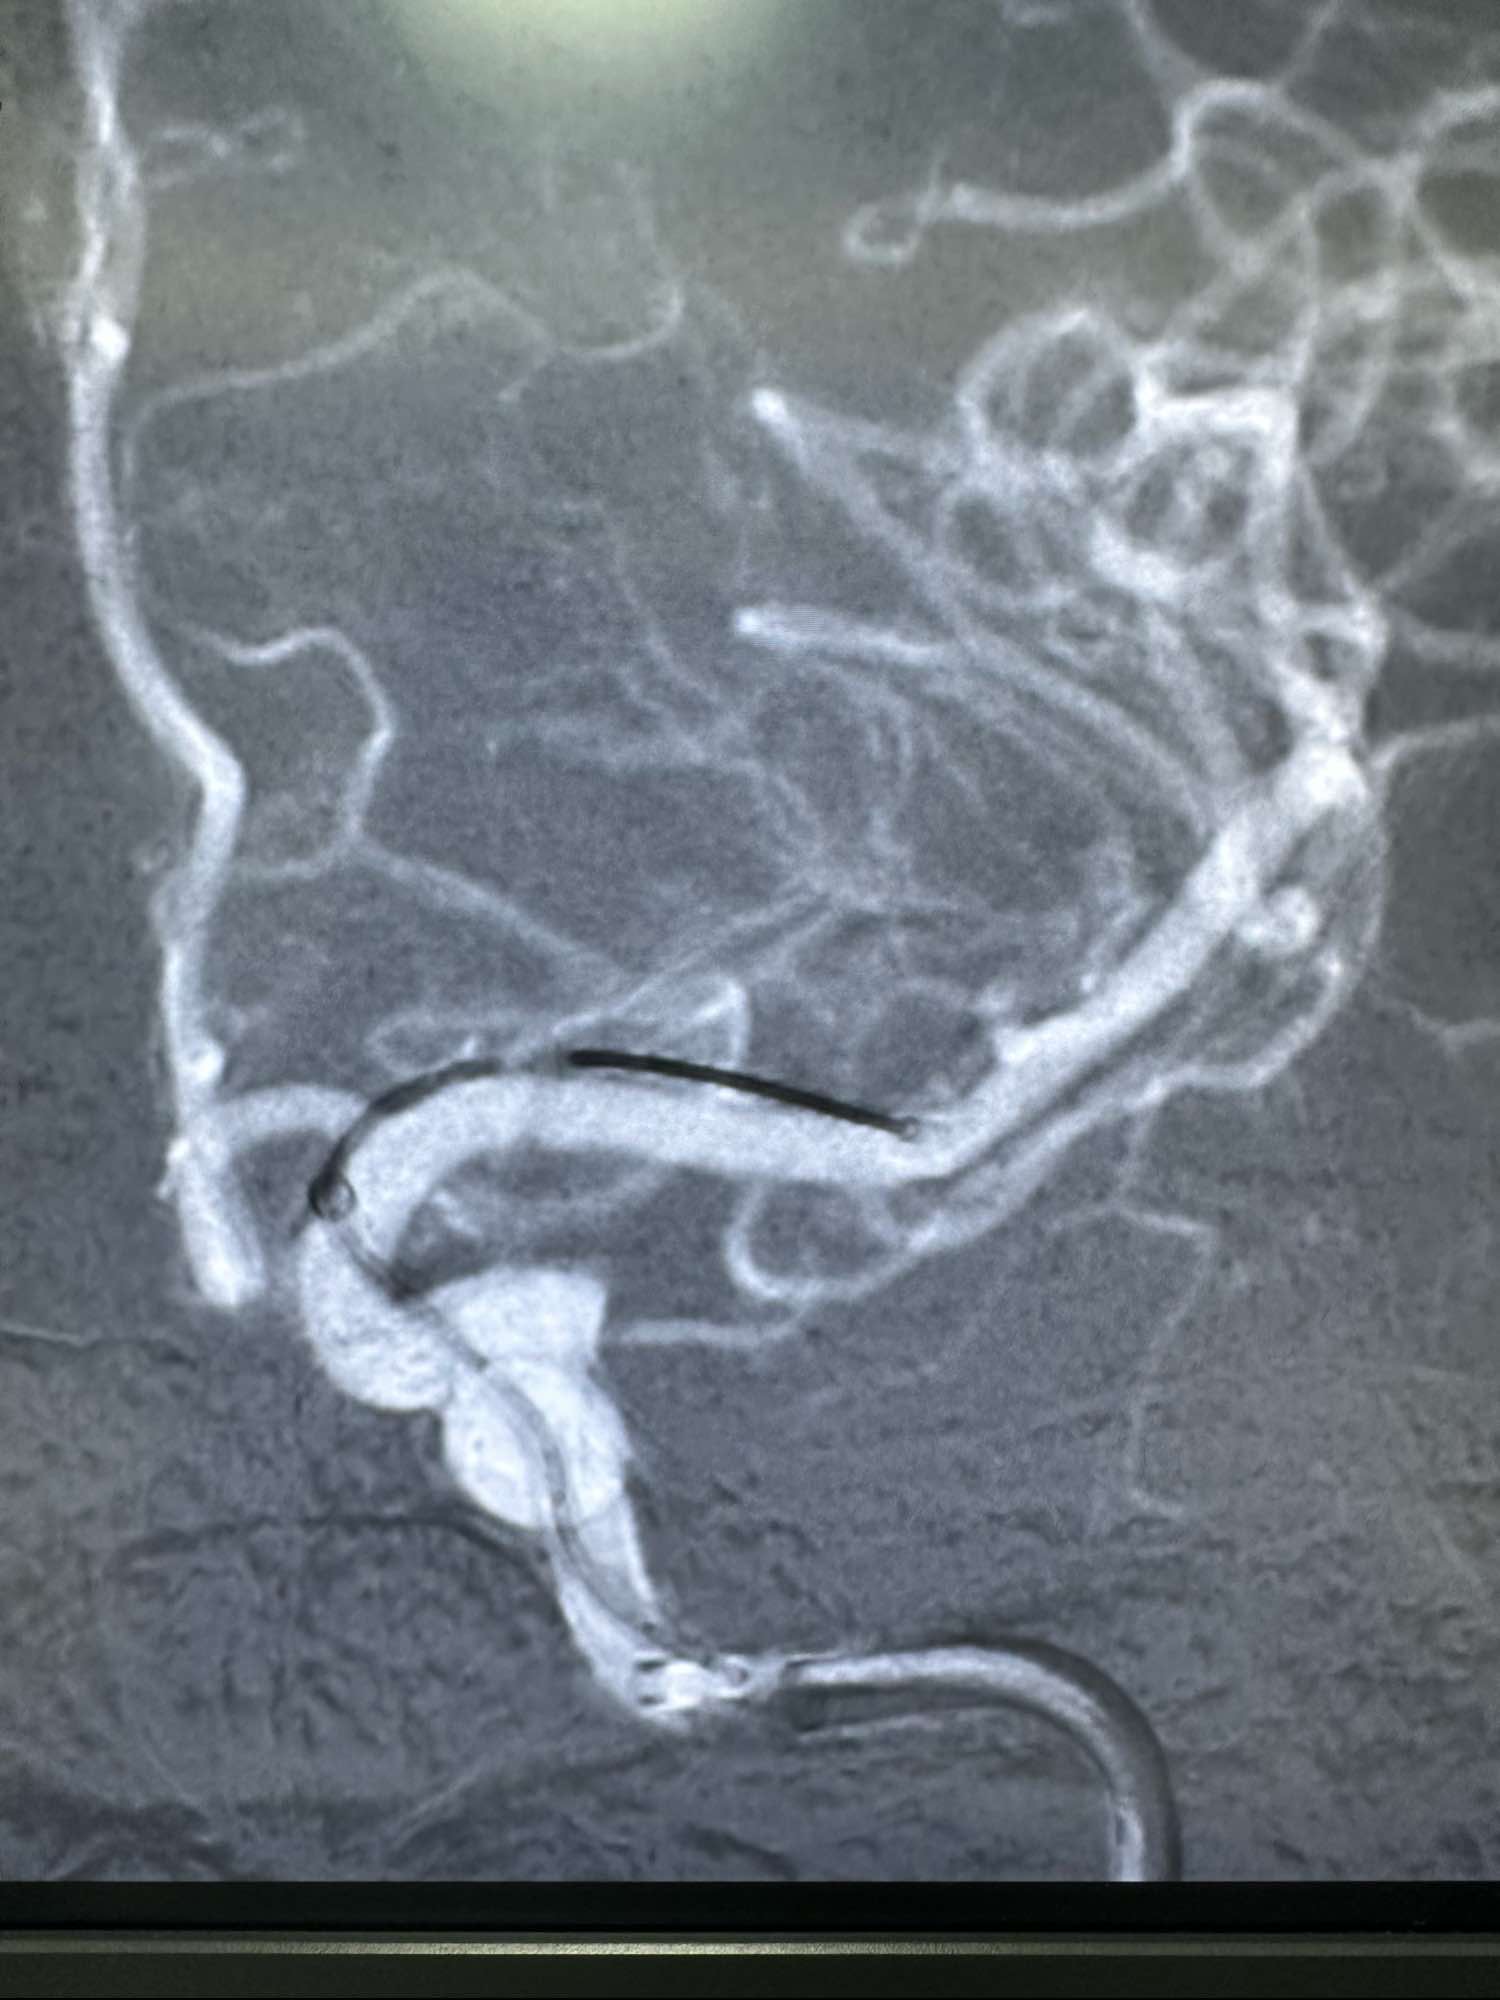

侧位